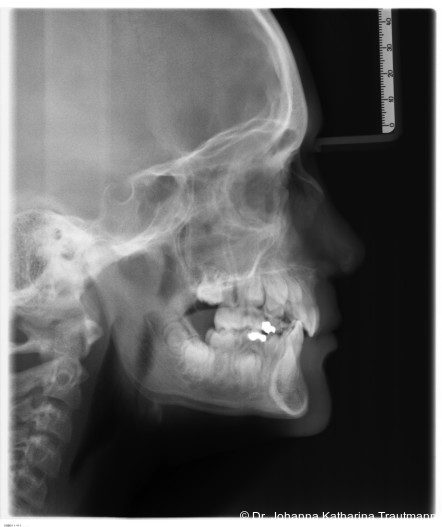

Das Fernröntgenseitenbild zeigte eine skelettale Klasse IIAnomalie mit einem Wits von 5,6 mm, bei einer tiefen Konfiguration (ML NL = 16,5°) mit bialveolär retrudierten Fronten (OK1NA = 5,9°; UK1NB = 10,4°), was sich auch in der Modellanalyse widerspiegelte. Hier zeigte sich zudem ein schmaler Oberkiefer mit multiplen Kippungen und Rotationen in der Front, einem hypoplastischem 22 sowie einer Mesialwanderung des 16. Des Weiteren zeigte sich eine asymmetrische Bisslage mit 1 PB distal rechts und ½ PB distal links bei einem Overjet von 2,5 mm sowie einem Overbite von 5 mm. Während im Unterkiefer bereits die zweite Zahnwechsel phase begonnen hatte, zeigte sich im Oberkiefer noch kein Wechsel in den Stützzonen. Gerade bei Patienten mit Spaltbildungen ist eine engmaschige Überwachung des Durchbruchs der oberen Eckzähne essenziell. Während bei der Allgemeinbevölkerung die Prävalenz von verlagerten Eckzähnen bei ca. 2,8 Prozent liegt2, ist diese bei Patienten mit Lippen-Kiefer-Gaumen-Spalten um den Faktor 10 erhöht.3, 4 Als klassische Risikofaktoren gelten zudem Platzmangel, transversale Enge aber auch Fehlstellungen, Nichtanlagen oder Hypoplasien der zweiten Schneidezähne. Diese übernehmen normalerweise die Funktion der Leitschiene für den S-förmigen Durchbruch der Eckzähne. Im vorliegenden Patientenfall kommen also mehrere Risikofaktoren für eine Verlagerung zusammen, was die rechtzeitige Diagnostik zur Abklärung einer Durchbruchsproblematik rechtfertigt. Da im Spaltbereich auch zusätzlich ein ausgeprägtes Knochendefizit vorliegen könnte, sollte auch immer die Option einer sekundären Osteoplastik abgewogen werden, deren Indikation und Timing optimal zum Durchbruch der Canini angepasst werden sollte.5